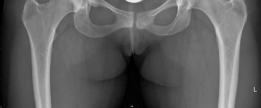

The radiographic evaluation of the dysplastic hip requires a highly standardized and rigorous protocol to accurately quantify the three-dimensional deformity. The initial assessment begins with a standing anteroposterior (AP) radiograph of the pelvis. In this patient, the AP view immediately reveals the hallmark signs of DDH: decreased anterolateral coverage of the femoral head and a broken Shenton line. The broken Shenton line—a step-off between the medial border of the femoral neck and the inferior border of the superior pubic ramus—indicates proximal and lateral migration of the femoral head due to structural instability. Furthermore, we observe an increased Tönnis angle (acetabular inclination) and a significantly reduced Lateral Center Edge Angle (LCEA) of Wiberg, confirming the diagnosis of severe lateral uncoverage.